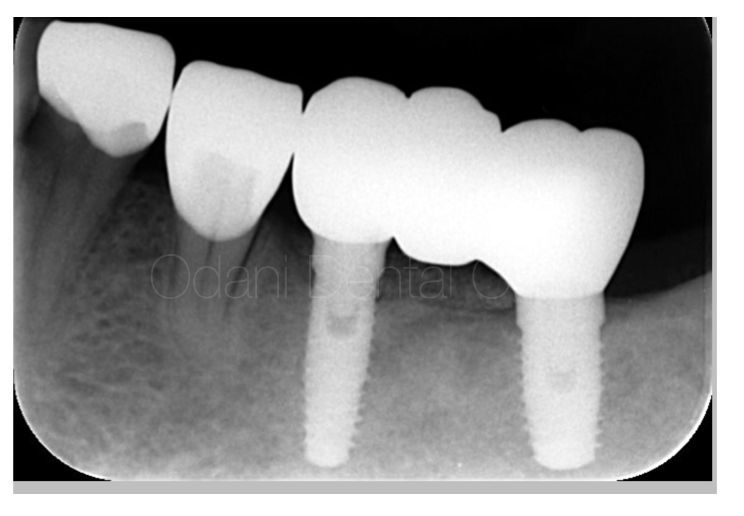

CT撮影

CT画像を見ると大きく骨が失われている状態でした。インプラントを用いた固定式の歯の修復を希望されましたが、このようなケースでは「骨を作る」という治療オプションが必要となることが多いです。

事前のCT画像によるシミュレーション通り、インプラント体を埋入するとインプラントのネジが大きく露出した状態(左写真)です。骨を作りたいところにチタン性のピンをテントの支柱のようなイメージで植立し、骨移植材を用いて骨造成を図りました(右写真)。